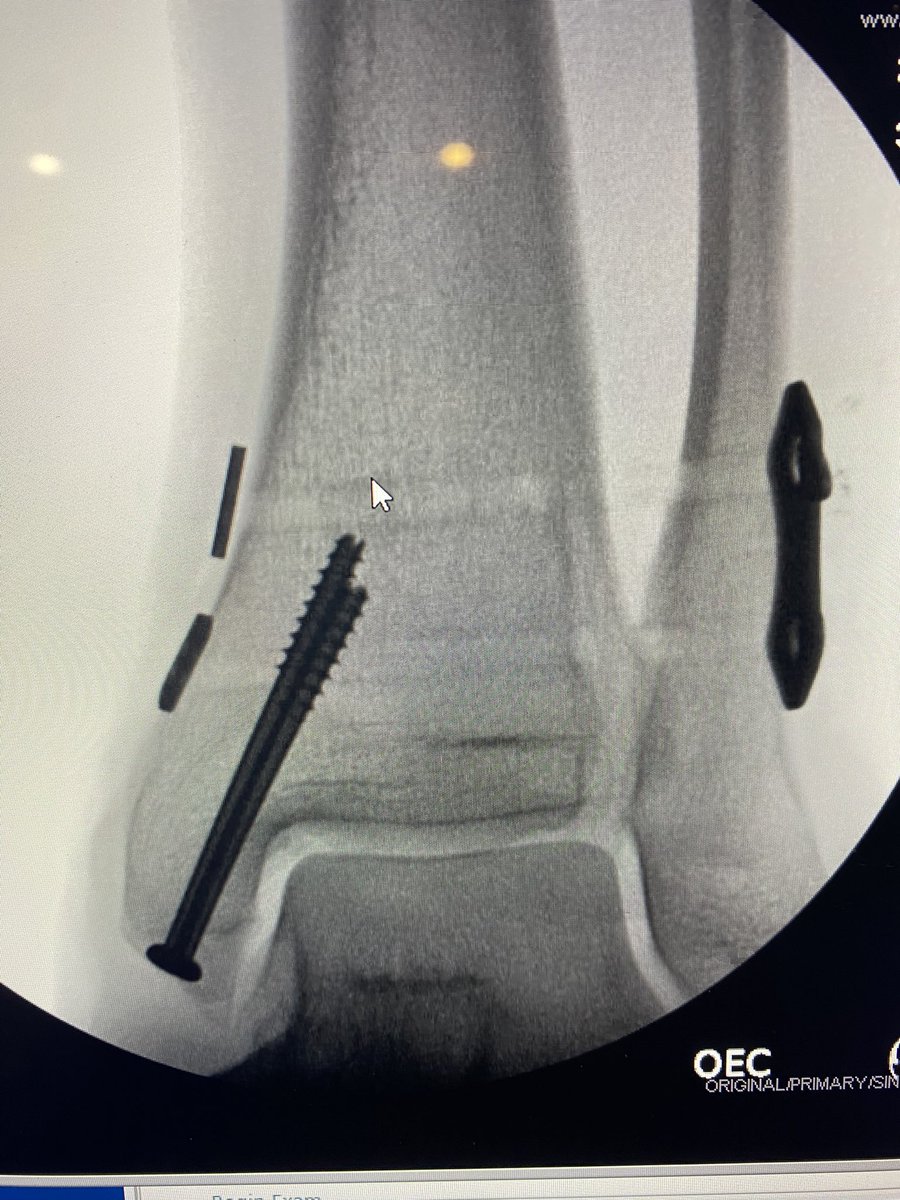

Similar case to @generalorthomd presented yesterday. Healthy 46 yo found some ice. Plan was to fix medial, and stress intra-op. @InvictaOrtho @BostonFootAnkle @pmangoneMD @traumaticum @StressHoop @DrAdamBitterman @DrBhavinJadav @generalorthomd @Davembmd @davidhcmd @MilanSenMD

English